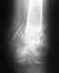

Из приложенных снимков (неизвестной давности) видны проблемы с тем бедром, где пластина, и с большеберцовой костью, фиксированной пластиной.

Желательно увидеть свежие рентгенограммы этих отделов. Не надо снимки сканировать офисными сканерами, сфотографируйте напросвет на негатоскопе или даже на фоне монитора с белым экраном.